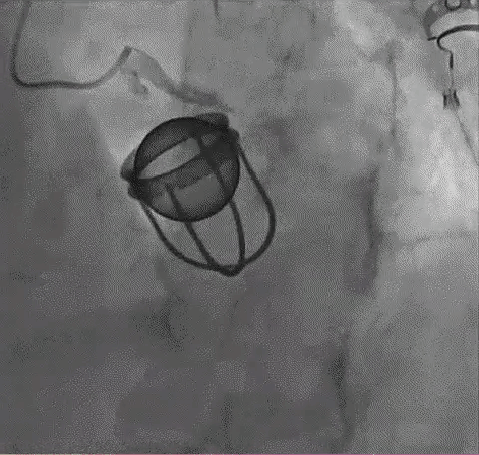

I am 49 … not out, how about you TAVI ?

Posted in Uncategorized, tagged prosthetic aortic valve, starr edwards valve, tavi valve on August 1, 2023|

This post was written after coming across a case report Oxford medical case report.

What is the life of a prosthetic Aortic valve?

The standard answer needs to be, mechanical valves can last up to 25 years or more. But, we are in a techno-conflict era. Instead of working on the longevity of the valve, ( with concerns for long-term OAC ) we fell for the biological valves. Curiously, this has made the durability of the valve, a less relevant discussion in many centers. We get excited when some company brings out a long-lasting bio-prosthetic valve that can live up to a maximum of 15 years.

Now, the biological valve comes in a new avatar ie TAVI, in a big way. Soon, we may celebrate an event free 10 years after TAVI. Going percutaneous is transformative. But at what cost? Fusion of metallurgy, chemistry, and pharmacology should make it possible for in-vivo metal valves to be safe for 75 years of human life span. The irony is we almost had one, One valve’s longevity was consistently exceeding the patient’s life span,(at least as far as we observed in the Rheumatic heart disease) This has been the star of all valves. We know what happened to that valve.

Final message

Most SE valves are implanted in the mitral position. Starr-Edward in an Aortic position working for 50 years is a big proof of reality. Of course, we can’t extrapolate with a single case report. We have stopped the production of these valves. So, there is no way to test it either. Anyway, cardiologists, cardiac surgeons, and finally the generation X, TAVI Innovators have something to learn from this case report. Forget Starr-Edwards, It looks like, there are some invisible forces that work against mechanical valves in recent times, which may not be good for our patients as of now. (There is something interesting related to this in Ref 2)

Future directions: Past need not be past

Nothing is impossible for our hyper-talented scientists, except probably in the “faculty of looking back” the past-Innovations (falsely labeled as obsolete) and bringing them again to optimal usage. If cardiologists feel surgical AVR injures their interventional pride, how about a percutaneous cage delivered at the root of the aorta, after ablating native leaflets, followed by an inflatable silicone ball?

Reference

A current 2023, opinion from the renowned Dr. Catherine Otto on this Mechanical vs biological valve , Indications, current usage pattern, the cut-off age, etc